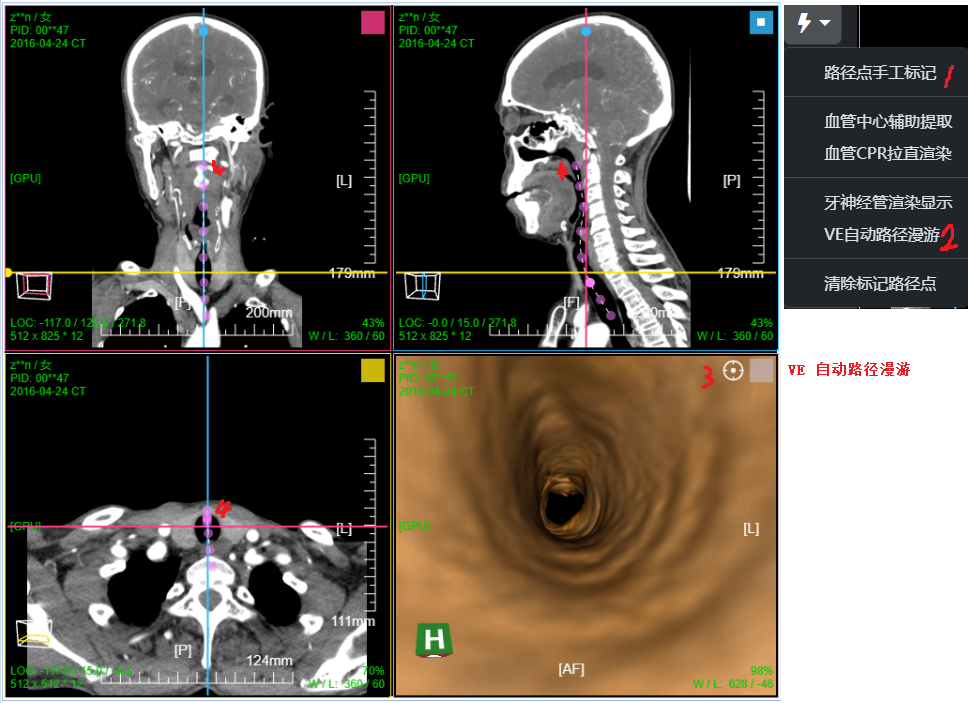

VE虚拟内窥; MPR十字交叉点移动到空腔处,点击右下角VE图标按钮, 进入虚拟内窥模式

1、首先菜单 选择 "路径点手工标记":在MPR平面上依次标记空腔管径的中心

三维:MPR多平面重建(支持任意旋转)、CPR任意曲线切面重建、MIP最大密度、VR容积重建、VE虚拟内窥;任意三维裁剪、一键去床、一键去头骨、快速旋转、厚切MPR(最大密度/最小密度/均值/VR); 手工/半自动分割,分割目标三维渲染; 肋骨CPR拉伸渲染、牙神经管渲染、血管CPR拉直渲染等